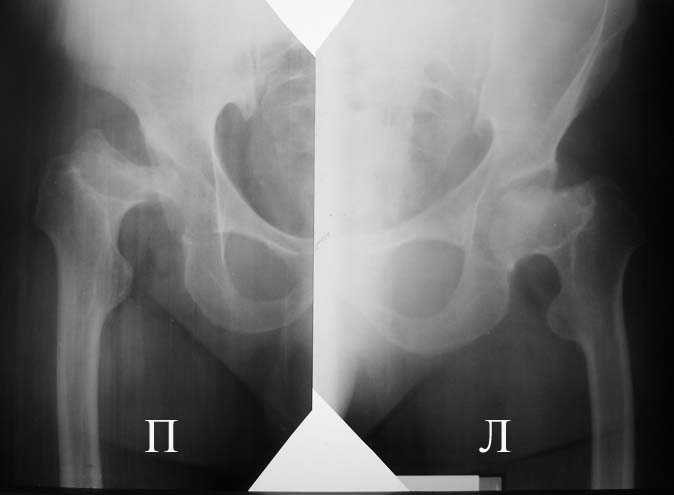

Аксиальная проэкция обоих т/б суставов

----------- следущая часть -----------

Вложение не в текстовом формате было извлечено…

Имя     : 2.jpg

Тип     : image/jpeg

Размер  : 23122 байтов

Описание: отсутствует

Url     : http://weborto.net:8080/pipermail/ortho/attachments/20090118/e452b84f/attachment-0004.jpg